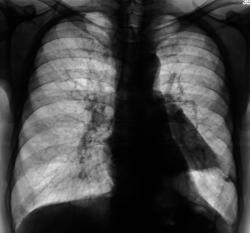

Пациент в 2008 году прошел плановую профилактическую флюорографию.

Сегодня, планово, регистратурой пациент был направлен на профилактическую флюорографию, предъявляет жалобы на наличие одышки.

Произведено дообследование.

Рентгенография и томография.

Плеврит.

Осумкованный пристеночный плеврит.

Пропунктировали, согласились "на осумкованный плеврит".

левосторонний плевральный выпот

Похоже на осумкованный, или как?